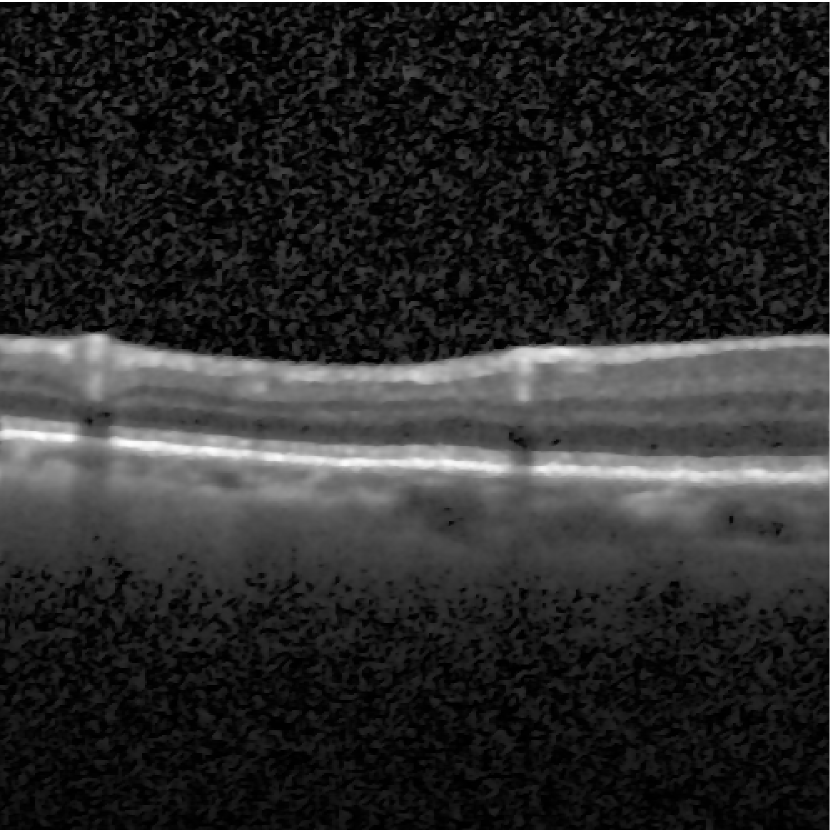

In this experiment, we apply the HALM algorithm to the EE model to denoise the corrupted optical coherence tomography (OCT) image. According to statistical optics, the noise in the OCT image is a multiplicative speckle noise. To recover a high-quality OCT image, we first perform logarithmic compression on the degraded OCT image, which makes the noise in the converted image additive. We denoise the transformed image by solving the EE model (1) with the HALM algorithm. Finally, we obtain the restored OCT image after exponential transformation.

We experiment with a synthetic OCT image generated by the Gaussian function provided in [11]. The variance of the speckle noise is 0.02. The HALM algorithm is compared with the HWC algorithm [11]. Figure 8(a) is the ground-truth OCT image, Fig. 8(b) is the noisy image, and Fig. 8(c) and (d) are denoised images by the HWC and HALM algorithm for the EE model, respectively. The HALM algorithm performs well at removing the noise and preserving features for the OCT image inferred from Figure 8. It renders better PSNR values than the HWC algorithm, since the PSNR value of the denoised image using the HALM algorithm is 27.48, and that using the HWC algorithm is 27.09.

We also test the HALM algorithm on denoising real OCT images from the large dataset of labeled OCT and chest X-ray images [12]. Two representative OCT images are selected from the dataset. The results are shown in Figure 9. The noisy images are displayed in the first row, and the corresponding denoised results using the HALM algorithm are shown in the second row. As illustrated in Figure 9, the HALM algorithm effectively reduces noise in the regions of interest while preserving important features and anatomical structures in the real OCT images.